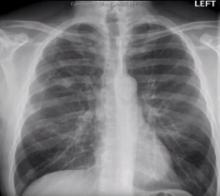

An asymptomatic patient was being followed for a central right upper lobe pulmonary nodule. After eight years, the nodule began to grow and a biopsy revealed it to be a benign hamartoma. Resection was recommended, but the hamartoma was not well suited for segmentectomy. Three dimensional reconstruction was used to develop a parenchymal-sparring procedure to resect the nodule without removing lung parenechyma.